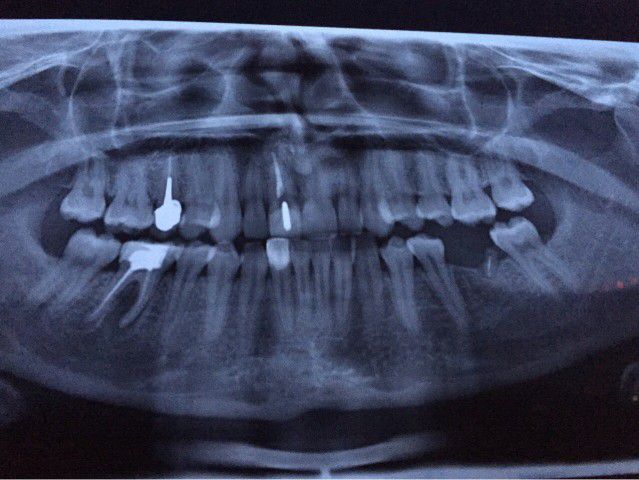

Увидеть зарождающуюся или уже сформированную кисту может только врач-стоматолог по рентген-снимку. Поэтому регулярные профилактические осмотры – не странная прихоть стоматологов, а реальная возможность своевременно начать лечение и спасти один или несколько зубов.

Зачастую наличие кисты зуба диагностируется случайным образом при проведении рентгенологического исследования (прицельного снимка зуба, ортопантомограммы, компьютерной томографии зубов).

Как уже отмечалось выше, диагноз кисты зуба подтверждается посредством рентгенологического исследования. На снимке отображается кистозная капсула, по очертаниям которой можно сделать вывод о размерах новообразования, степени поражения кости челюсти, состояние корня и корневых каналов.

10-летний мальчик был направлен в отделение челюстно-лицевой хирургии для оценки боли и отека в левом преддверии нижней челюсти.При физикальном обследовании обнаружено твердое подслизистое образование с расширением кортикальной пластинки в области второго премоляра. Панорамная рентгенограмма показала четко выраженное рентгенопрозрачное поражение размером примерно 3 × 2 см в диаметре, включая коронки 2-го левого премоляра нижней челюсти, не прорезавшегося. В поражение также были вовлечены корень соседнего клыка, 1-й премоляр и 1-й моляр. Корневые вершины этих зубов еще не закрылись. Признаков резорбции корня не было (). Учитывая возраст пациента и близость к нижней границе нижней челюсти, планировалась марсупиализация кистозной полости с сохранением всех пораженных зубов.Интраоперационно () из-за чрезмерной подвижности 2-го премоляра зуб не удалось сохранить. В послеоперационном периоде для предотвращения опрокидывания 1-го премоляра и моляра в дефект был установлен фиксатор пространства.

Ортопантомограмма (OPG) показала большое рентгенопрозрачное поражение с прорезыванием 2-го премоляра в левой части тела нижней челюсти

Случай 1 предоставляет информацию о скорости роста воспалительных зубных кист: за трехлетний период киста достигла диаметра 3 см (рис. 1а, б). Shear 1 рентгенологически показала, что зубные кисты диаметром 4–5 см могут развиться через 3–4 года.

При клиническом обследовании у пациентки остались все постоянные зубы и сохранен левый второй первичный моляр нижней челюсти. Рентгенологические записи включали ортопантомограмму, боковую цефалограмму, задне-переднюю цефалограмму и рентгенограмму запястья. Ортопантомограмма выявила четко выраженное рентгенопрозрачное поражение на левой стороне нижней челюсти, окружающее непрорезавшийся левый второй премоляр нижней челюсти, который, по-видимому, был наклонен мезиально ниже оставшегося первичного второго моляра.Корень соседнего премоляра был включен в поражение, но резорбции корня не наблюдалось (рисунки 1 и 2).